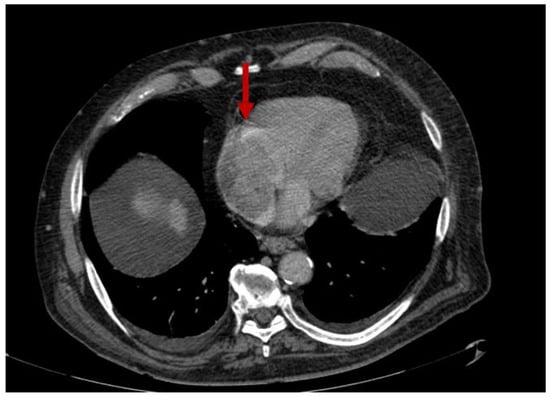

2.1.2. Pulmonary Arterial Manifestations

2.1.3. Systemic Veins

2.3. Mediastinum and Heart